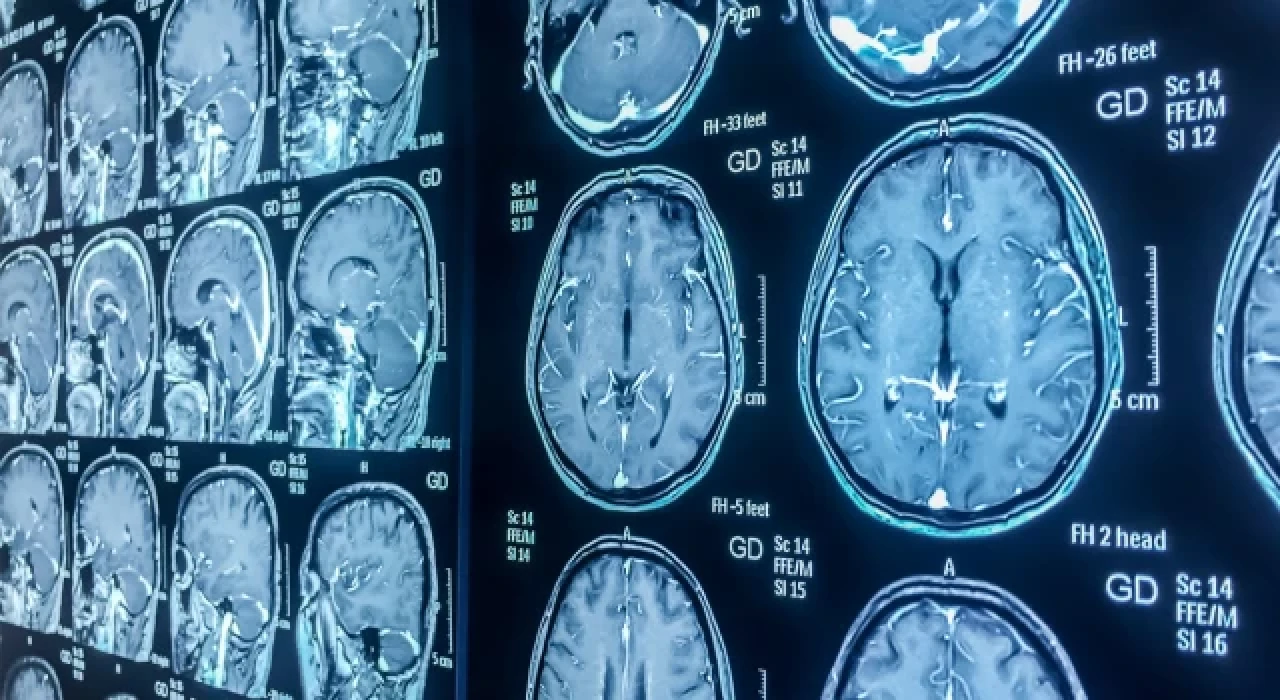

Muhalif. SAĞLIK Beyin kanseri, kan testi ile erken teşhis edilebilecek

Beyin kanseri, kan testi ile erken teşhis edilebilecek

Bilim insanları, beyin kanserini erken evrede tespit etmek için dünyada ilk kez geliştirilen bir testin tanıda devrim yaratabileceğini, tedaviyi hızlandırabileceğini ve hayatta kalma oranlarını artırabileceğini açıkladı.

İngiltere'de bir araştırma ekibi, beyin kanserinin en ölümcül türlerine sahip hastaların bile çok daha hızlı teşhis edilmesine yardımcı olabilecek, potansiyel olarak onları invaziv ve yüksek riskli cerrahi biyopsilerden koruyabilecek basit bir kan testi tasarladı. Buluş, Uluslararası Kanser Dergisi'nde bildirildi.

Testin özellikle "erişilemez" beyin tümörleri olan ve tedaviye mümkün olan en kısa sürede başlamanın hayati olduğu hastalar için faydalı olacağı bildirildi.

Imperial College sağlık hizmetleri tarafından yönetilen Beyin Tümörü Araştırma Merkezi'ndeki araştırmacılar, testin, en sık teşhis edilen yüksek dereceli beyin tümörü türü olan glioblastoma (GBM) dahil olmak üzere bir dizi beyin tümörünü doğru bir şekilde teşhis edebildiğini açıkladı. Ekip, testin "yüksek analitik hassasiyete ve kesinliğe" sahip olduğunu bildirdi.

Beyin Tümörü Araştırmaları kuruluşunun genel müdürü Dan Knowles"Bu çığır açıcı araştırma, beyin tümörü hastalarında daha erken tanıya ve daha iyi sonuçlara yol açacak. Sonuçları doğrulamak için daha fazla araştırma yapmayı planlıyoruz ve eğer başarılı olursak hastalar iki yıl gibi kısa bir sürede yeni testten faydalanabilecek" dedi.

Datar Cancer Genetics'in finansmanıyla geliştirilen TriNetra-Glio kan testi, tümörden kurtulan ve kanda dolaşırken bulunan glial hücreleri izole ederek çalışıyor. İzole edilen hücreler daha sonra boyanarak mikroskop altında tanımlanıyor.

Beyin Tümörü Araştırma Merkezi'ni yöneten Dr. Nelofer Syed şunları söyledi:

“Bu teknoloji sayesinde ulaşılması mümkün olmayan tümörlerin tanısı, risksiz ve hasta dostu bir kan testiyle mümkün hale gelebiliyor. Şu anda bu tür tümörler için invaziv olmayan veya radyolojik olmayan testler olmadığından bunun dünyada bir ilk olacağına inanıyoruz."